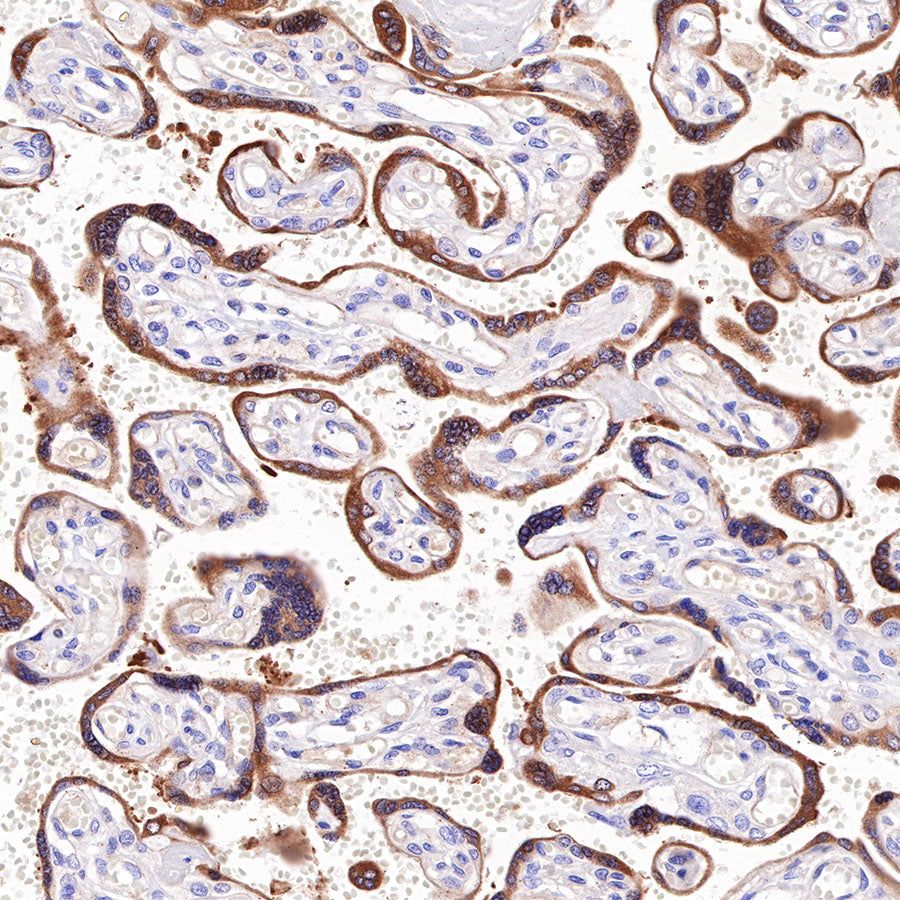

Picture

Picture

Immunohistochemistry